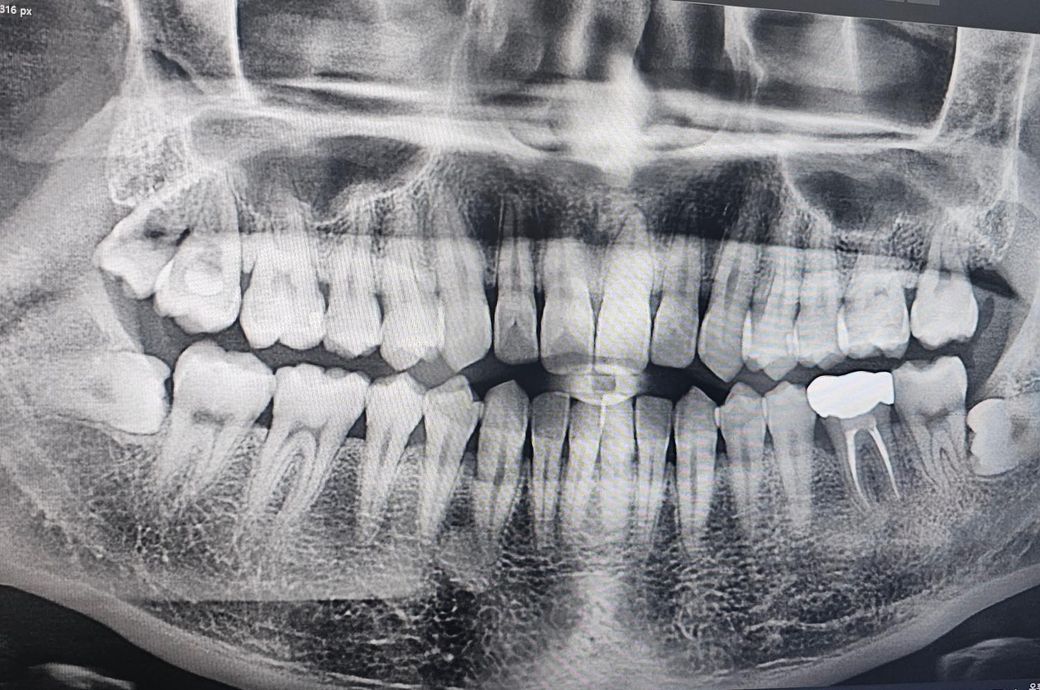

인접면충치 전문가분들의 의견이 궁금합니다

크라운5개+인레이4개(4개중3개는 크라운권장)+레진+잇몸치료+윗쪽 왼쪽 사랑니 발치

대부분 레진 인레이(그중 하나는 크라운할수도) +잇몸치료+사랑니발치

첫번째병원에선 즉 크라운7~8개를 하라고하셨는데 내이빨을 너무 많이 갈아내야 하는게 아닌가... 싶고

두번째병원에선 의사마다 견해와 처방이 다르다 이전병원은 충치인지 아닌지 약간만 의심되도 일단 갈아내고 없애야한다는 판단인거같다고 말씀하셨고 두번째병원에서는 인접면충치가 확인하기 힘들 뿐더러 갈아냈는데 충치가 아닐수도있다~ 라고 애매모호하게 말씀하셨어요

현재 오른쪽 아랫니 (아마46번?) 빼고는 시리거나 아픈건 없습니다

두번째 치과에서 하신 말씀이랑 다들 비슷한 의견일꺼에요. 치과의사마다 치료 하는 방법이 다르기 때문에 어떤게 옳다고 말씀드리기가 어렵습니다. 사진상으로 인접면에 충치가 없는건 아니고 의심되는 치아들이 많이 보이긴하니 계속해서 의심이 드신다면 불편한 치아만 치료를 먼저 하시고 나머지는 지켜보시면될것같습니다.

사진으로만 보기에는 큰충치가 보이지는 않습니다.